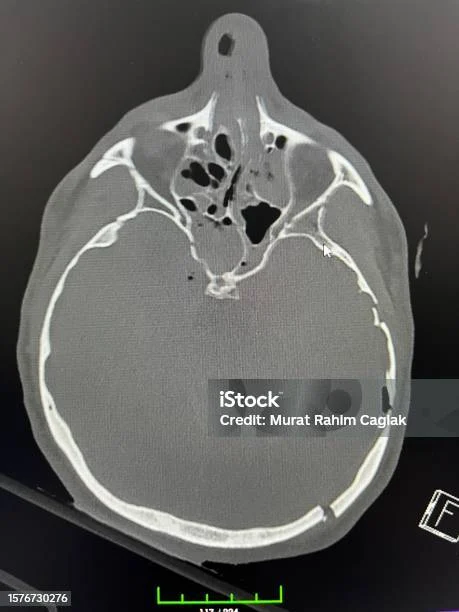

Seiring berjalannya waktu, kondisi bayi menunjukkan perbaikan signifikan. Pada hari kelima, hasil CT scan kontrol memperlihatkan penurunan ukuran hematoma dan stabilisasi retakan pada tulang tengkorak. Dokter kemudian memutuskan untuk menghentikan kateter dan melanjutkan perawatan konservatif, termasuk fisioterapi ringan untuk meningkatkan tonus otot dan stimulasi sensorik.